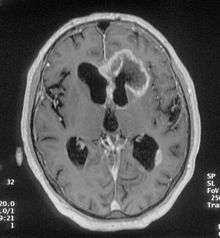

There are many different causes of frontal lobe epilepsy ranging from genetics to head trauma that result in lesions in the frontal lobes. Although frontal lobe epilepsy is often misdiagnosed, tests such as prolonged EEG monitoring and/or a MRI scan of the frontal lobes can be administered in order to reveal the presence of a tumor or vascular malformation. Unlike most epileptic EEGs, the abnormalities in FLE EEGs precede the physical onset of the seizure and aid in localization of the seizure's origin.[3] Medications such as anti-epileptic drugs can typically control the onset of seizures, however, if medications are ineffective the patient may undergo surgery to have focal areas of the frontal lobe removed.